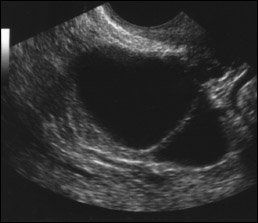

Ultrasound images of a single thin septated cyst (top); a single thick septated cyst (middle); and multiple septated cysts (bottom). Image courtesy of Edward J. Pavlik, director of research in gynecologic oncology, UK Ovarian Screening Research Program.